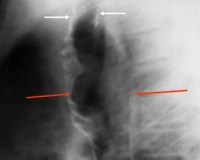

• Рентгенодиагностика: на простых рентгенограммах легких выявляют вторичные изменения легочной паренхимы, сильно расширенную трахею, диаметр которой превышает диаметр позвоночного столба. Для уточнения состояния ТБД и степени поражения проводят бронхографию. Более точную рентгенологическую картину получают при КТ легких, выявляющей патологическое расширение дыхательных путей (диаметр трахеи >25-27 мм у мужчин и 21-23 мм у женщин).